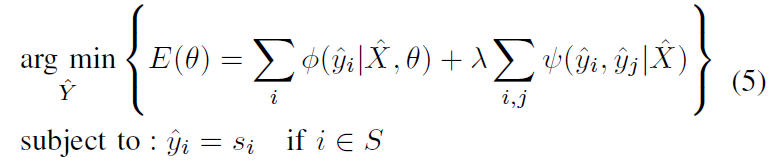

此时就可以将优化目标函数(1)分解为两步,一是 label update step,二是 network update step:

(1)label update step

对分割目标

Y

^

\hat Y

Y^ 进行单独优化:将网络参数

θ

\theta

θ 固定,这样优化目标(1)简化成 CRF 问题:

为方便实现,将等式(5)转换为无约束优化等式: